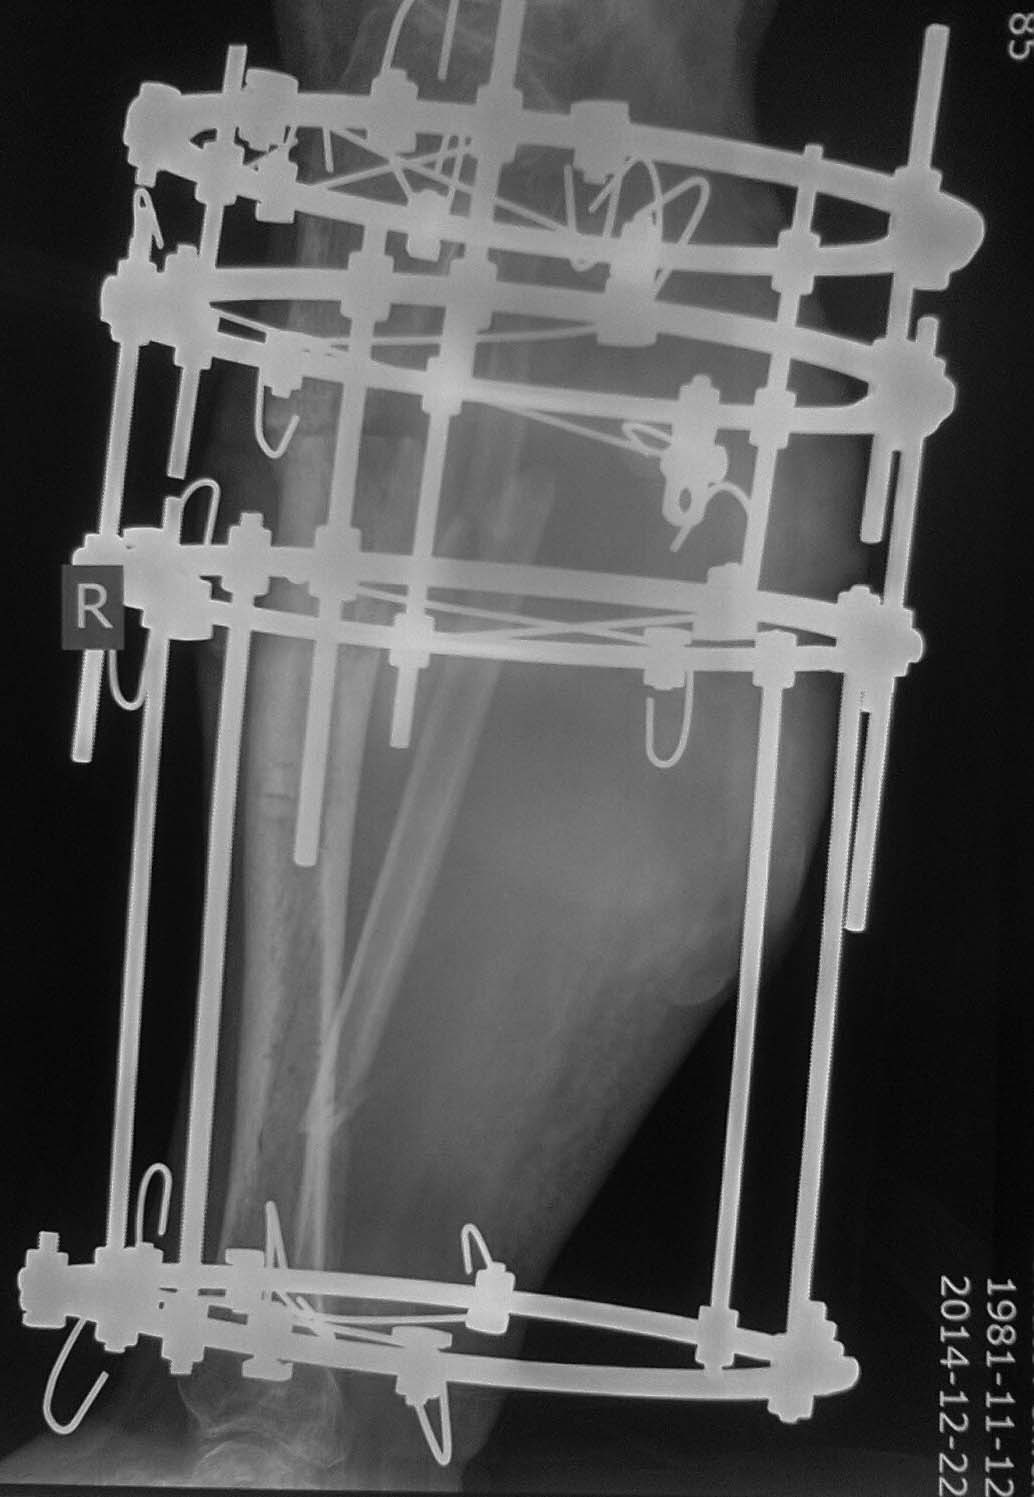

Доброго времени суток, уважаемые коллеги!Прошу Вашей помощи в лечении пациента Н. Пациент, 33 г. Травма в мае 2014 года в результате ДТП (сбит машиной). Оперирован в институте (или центре) травматологии и ортопедии одной из среднеазиатских республик (уроженец этой республики). Обратился к нам в августе, по поводу наличия гнойной раны внутренней поверхности голени с обильным отделяемым. (Рентгенограммы- фото 1). Выполнено: остенекрсеквестрэктомия, резекция концов отломков, перемонтаж аппарата (фото 2). Рана успешно зажила, пациент исчез из вида. Неделю назад пришел снимать аппарат с рентгенограммами (фото 3,4). Ходит с полной безболезненной нагрузкой на конечность, АВФ стабилен, раны от опорных элементов спокойны, отек конечности умеренный, в проекции бывшей гнойной раны- втянутый рубец (если необходим внешний вид конечности, то смогу выложить на следующей неделе,наверное). Учитывая большой дефект кости по задней поверхности кости, боимся, что при нагрузке без аппарата произойдет перелом. Вопрос: что делать? Наши варианты: 1.снять АВФ, рассверлить канал, установить штифт с антибактериальной мантией в виде "протеза" кости; 2.Резекция дефектного участка, остеотомия в н/3, перемонтаж АВФ и билокальное замещение дефекта. Что Вы посоветуете? Спасибо всем откликнувшимся.

Доброго времени суток. К сожалению работа в аппарате без остеотомии МБк ничего не даст. насколько после операции стала короче голень? Учитывая смещение малоберцовой кости скорее всего 2,5-3 см. Думаю, можно смело говорить о ложном суставе. 2 вариант предпочтительнее при желании пациента. Расцените как вариант: ревизия ложного сустава, краевая резекция отломков, репозиция с замещением дефекта аутокостью, синтез пластиной + правильная а\б терапия. И удача))